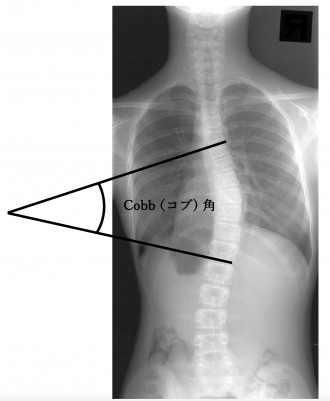

Cobb角という指標を使います。

脊柱の上下で最も曲がりの強い椎体から直線を伸ばしていき、角度を測るものです。Cobb角が10度以上の場合に側弯症と診断されます。

検査では、レントゲンでCobb角を測定し、進行度を評価します。

診断は端的に言えばCobb角が10度以上であることです。